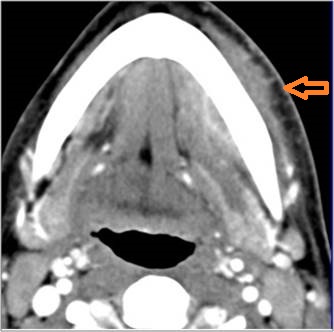

There is evidence of a developing abscess at the periphery of the lymphoid tissue of the palatine tonsil within the potential peritonsillar space. [Yes/No]